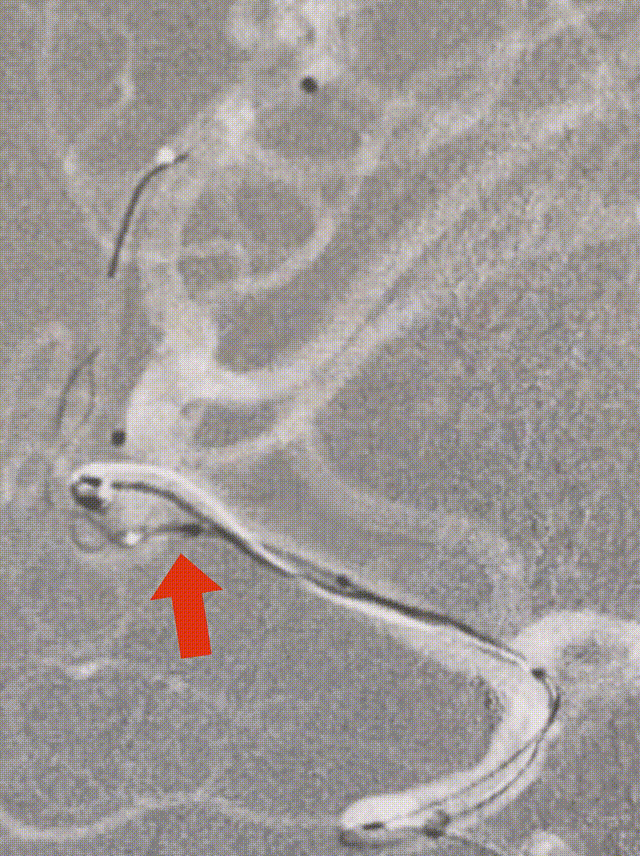

造影提示:动脉瘤瘤颈累及上下干支,下干支与M1成角较锐S弯;患者右侧颈内动脉非常迂曲。

3D造影成像:动脉瘤大小约3.7*3.1mm。

因下干支与M1成角太锐,支架在转弯处打开,多次推拉调整,以“神龙摆尾”方式释放,将支架尾端避开上干开口。